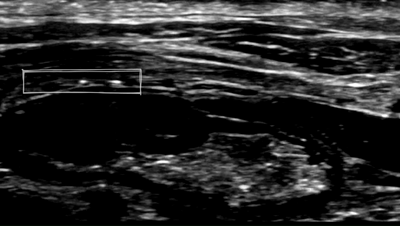

Bioabsorbable Sticker被制成柔軟的微小貼紙形狀。當(dāng)Bioabsorbable Sticker植入到吻合口處時(shí)會(huì)隨著身體 pH 值變化而改變形狀,這樣就可以對(duì)胃腸手術(shù)之后并發(fā)癥(例如吻合口滲漏)進(jìn)行早期預(yù)警。臨床醫(yī)生可以通過(guò)超聲成像實(shí)時(shí)查看Bioabsorbable Sticker形狀變化。

之所以Bioabsorbable Sticker能夠在超聲下看得見(jiàn),主要Bioabsorbable Sticker上微小金屬片會(huì)隨著凝膠形變,聚集或者分散。超聲就根據(jù)微小金屬片聚集或者分散來(lái)判斷胃腸、胰腺的吻合口是否發(fā)生泄漏。